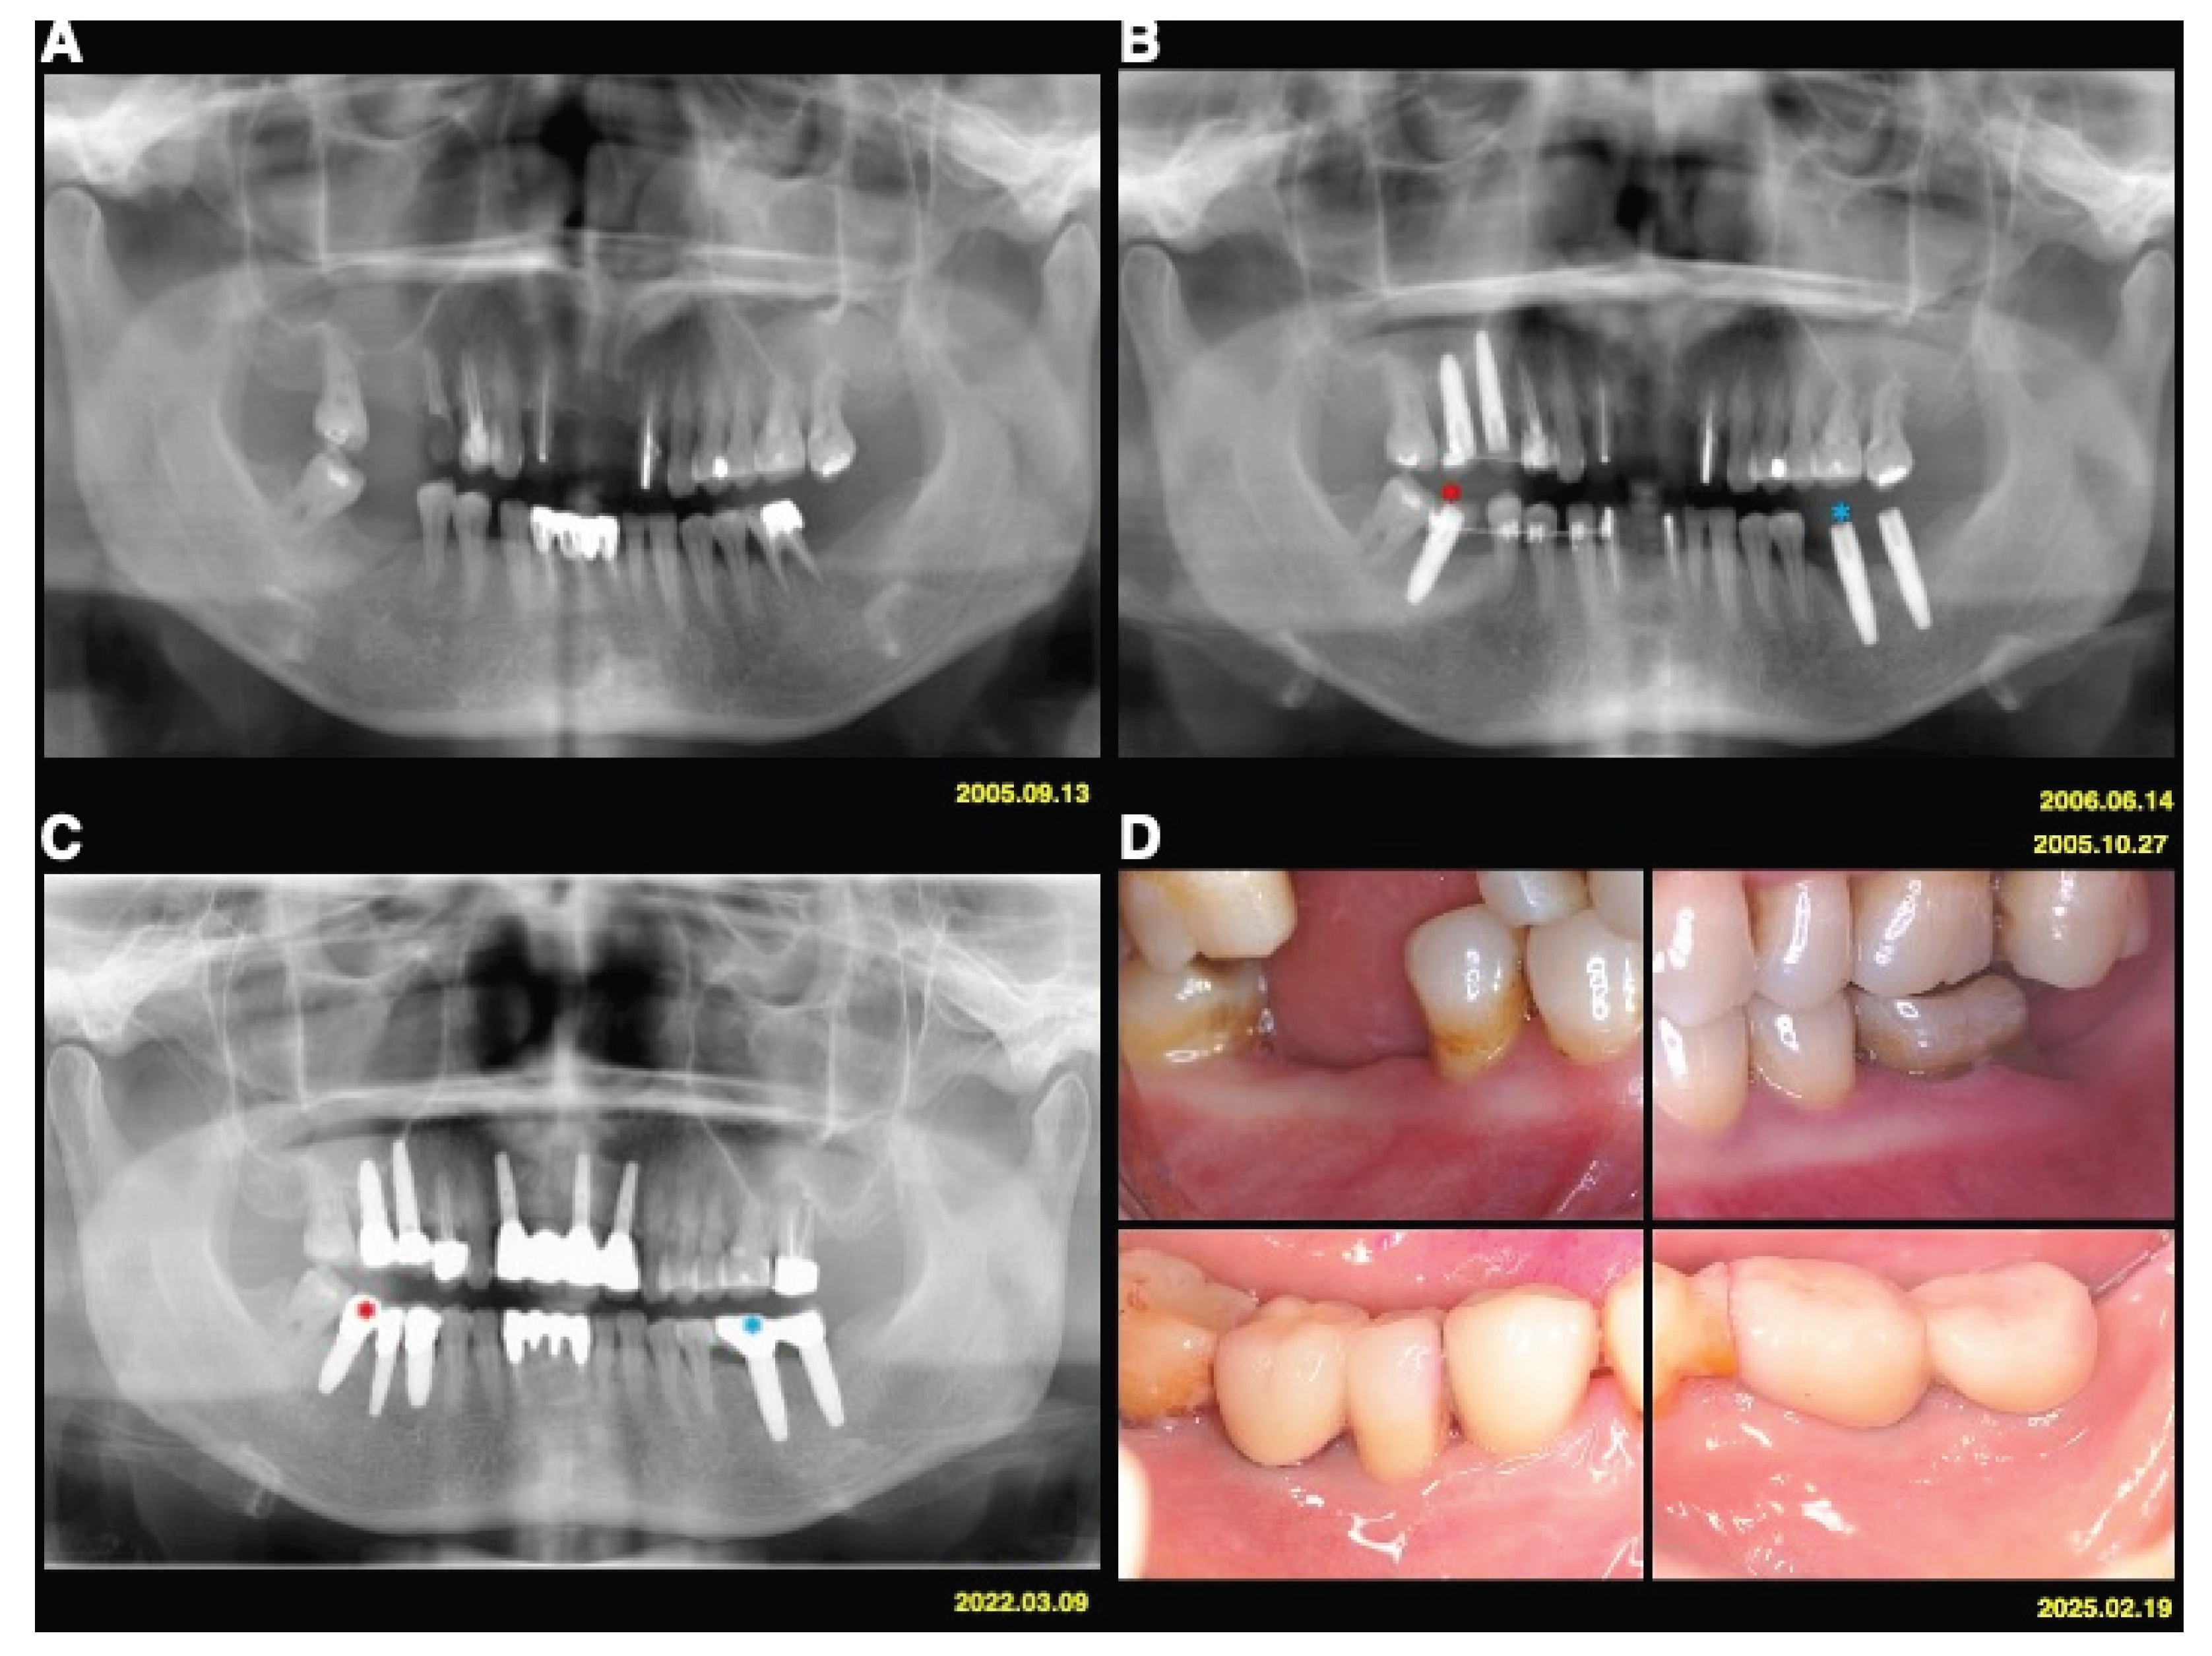

The test implants served as absolute orthodontic anchorages to facilitate molar uprighting, tooth retraction and realignment, or implant site development, whereas implants used exclusively for prosthetic purposes served as controls (Figure 1 and Figure 2). The use of implant anchorage significantly supported orthodontic treatment in patients with periodontally compromised dentition. A key advantage of this combined orthodontic-prosthetic approach was that the implants play a dual role, providing both anchorage and functional rehabilitation.

Figure 1. Case 1 (A) A 55-year-old female patient with stage IV periodontitis requested full-mouth reconstruction. (B) Dental implants were used for dual purposes: as orthodontic anchorage and as part of the oral rehabilitation of a periodontally compromised dentition. Test implants (red star) served as absolute orthodontic anchorage to facilitate molar uprighting, tooth realignment, or implant site development, while implants used exclusively for prosthetic purposes (blue star) served as controls. (C) Radiographic findings from 2022 showed no signs of periodontal or peri-implant bone loss. (D) Clinical outcomes 20 years post-treatment demonstrated healthy and stable periodontal and peri-implant tissues.